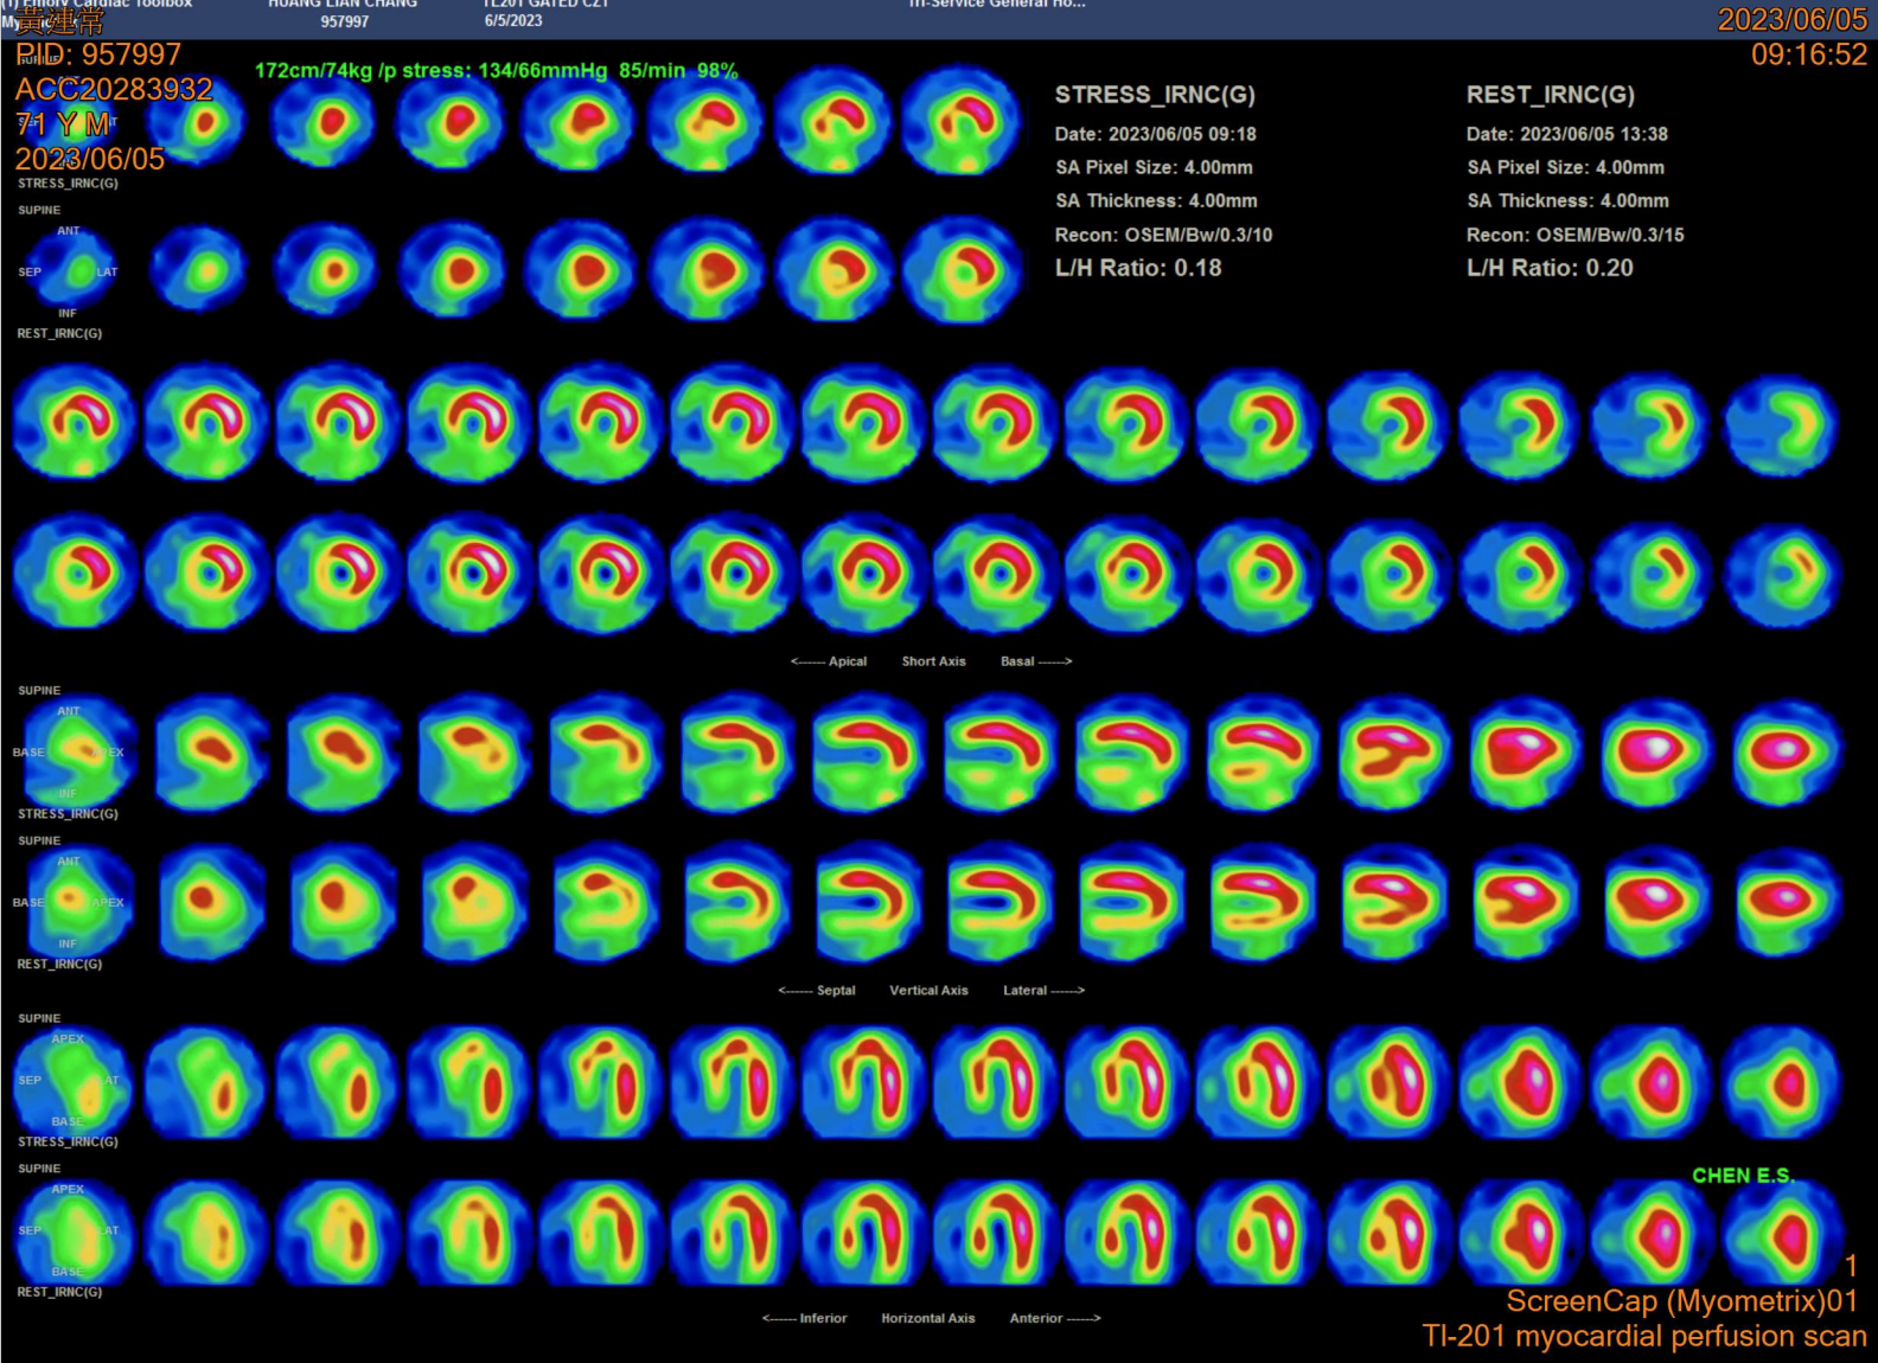

Relevant Test Results Prior to Catheterization

LDL 85 mg/dL; HbA1c 7.6%; Cre 1.1 mg/dL

Diagnosticcoronary angiography revealed: Chronic total occlusion (CTO) in the rightcoronary artery (RCA) with heavy calcification; Diffuse lesion in the leftanterior descending (LAD) artery; Proximal lesion in the left circumflex (LCx)artery; LAD providing collateral flow to the RCA.